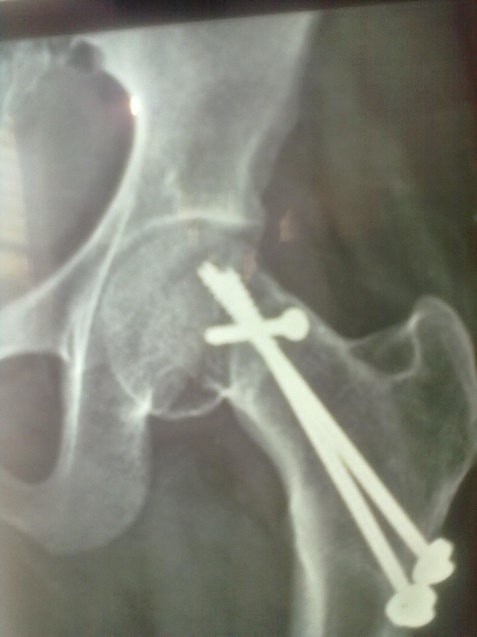

Result: Most of the cases showed union in 16 to 24 weeks. In one case there was implant failure.

Spinal block was used in the procedure. Prone position on fracture table with radiolucent top was used. Fracture site was exposed through posterior approach and sclerosed margins of the fragments were freshened. Fracture was reduced with appropriate neck shaft angle and fixed with Moors pin/ knowels pin or 4 mm /7mm partially threaded cancellous screws. Any rotation or tilt was corrected. The fixation was augmented with quadratus femoris muscle pedicle bone graft harvested from intertochateric crest area with a bone pedicle of length 2 cm, width 1 cm and depth 1 cm. The graft was secured to the proximal femoral head fragment with 3.5mm cortical screw or 4mm cannulated cancellous screw. Soft tissue closure was done over drain.

Patients were followed up at 2 weeks, 4 weeks, 6 weeks, 8weeksk, regularly at 6 week interval for next 6 month and then at three month interval up to two year. Radiographic analysis was performed at each follow up with special attention to extent of callus formation, alignment of fragments and hard ware integrity.